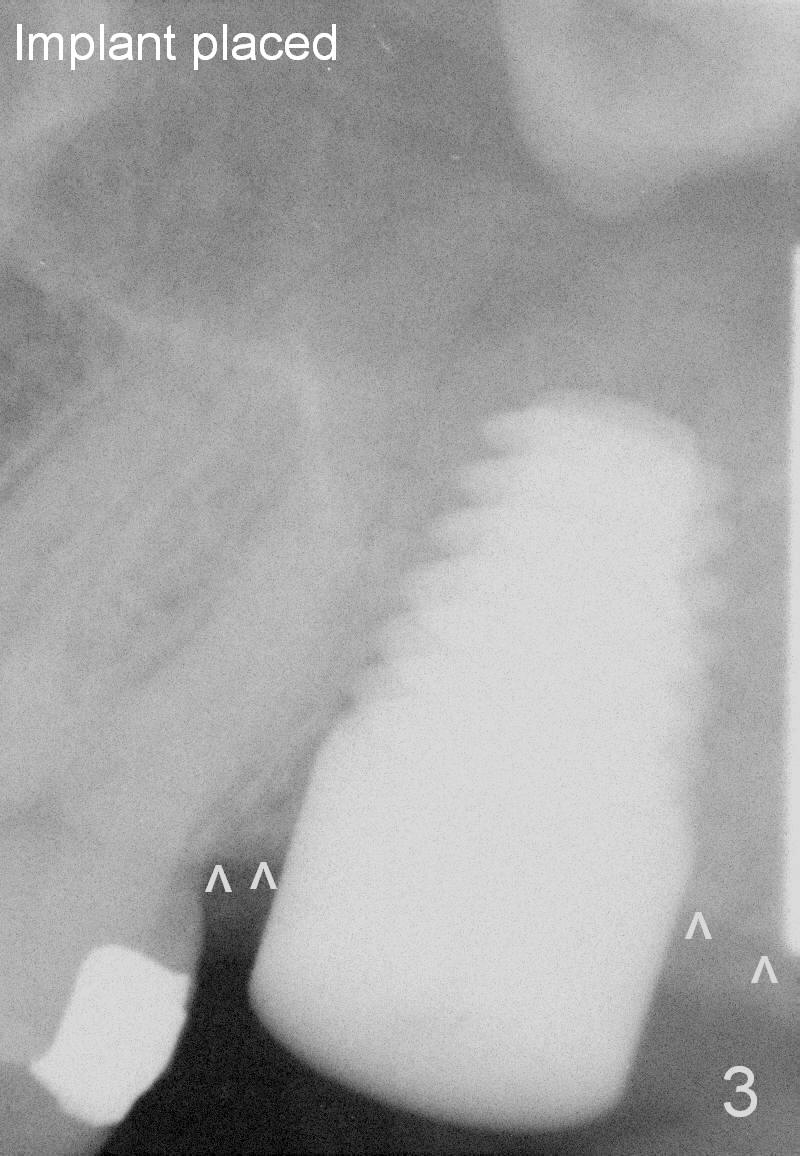

The tooth #15 is going to be extracted due to repeated furcal infection; the distal crest appears to be flat (Fig.1 ^). Two and a half months post extraction, a 6x17 mm tap is placed (Fig.2) prior to placement of a 8x14 mm tissue-level implant (Fig.3). It is apparent that the crest bone has started bone loss (^).